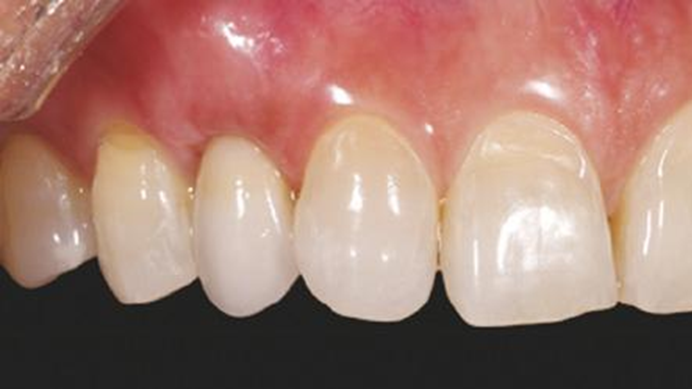

Clinical case: BPET PREDICTABILITY - State-of-the-Art SOCKET SHIELD

- Courtesy of Dr. Howard Gluckman, South Africa -

“AnyRidge is perfect for the anterior esthetic zone due to its strong initial stability & fast osseointegration.

Plus, KnifeThread® ensures space maintenance when using the PET/Socket Shield/Root Membrane Technique, showing excellent bone growth.”